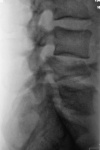

Крестец, боковая.

пишут не рентгенологи, а клиницисты. О сдавливании элементов хвоста, кроме клиницистов, могут еще судить магниторадиологи. Наш (общий на всех) термин - стеноз позвоночного канала. Еще надо не лениться и указать степень компрессии компрессии тела - легкая (20-25%), умеренная (25-40%), выраженная (больше 40%). А также замерить расстояние между основаниями дуг позвонков в прямой проекции - у L4 оно явно шире, и тогда в дополнение к перелому тела добавится перелом дуги и термин "нестабильный". Для полной красоты следует указывать угол кифотической деформации; критическими значениями являются:  для шейного отдела - 11º,  для грудного – 40º,  для поясничного - 25º

Изобразить не могу, но определение дам: Определение степени кифотической деформации - на боковых рентгенограммах измеряют величину угла, образованного при пересечении двух линий, которые проводятся по задней поверхности тел выше- и нижележащих позвонков, образующих кифоз.